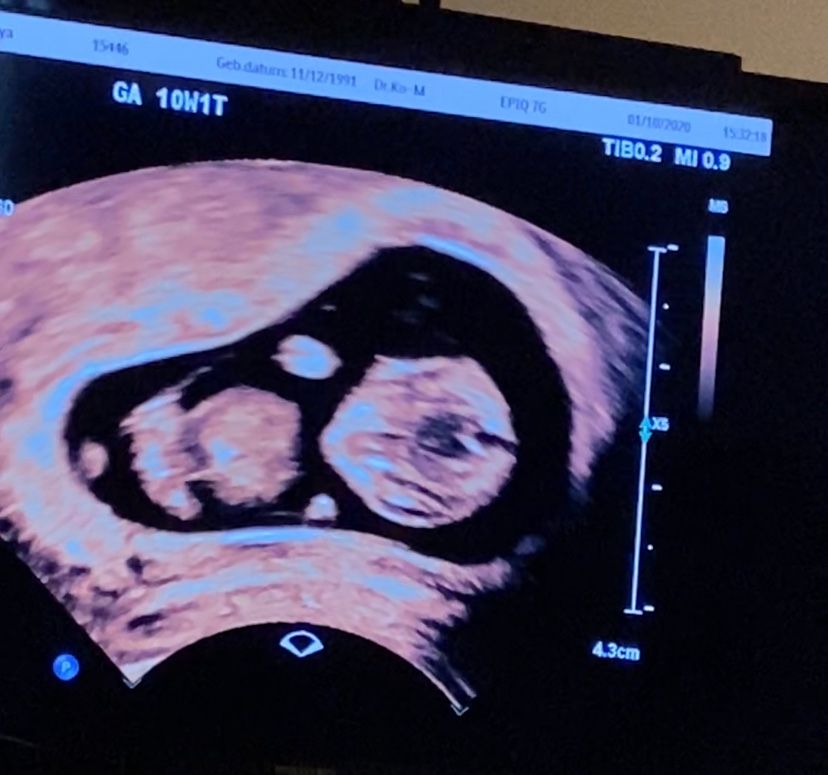

10 недель и 1 день.

Беременность- 1 триместр ( только до 10 недель)Девочки , это половой бугорок? Или рано?ещё не понятно кто там?😅

Рано очень, в 12-13 недель гляньте. А смотрят бугорок в профиль, а тут лицом, насколько понимаю.

Попросите на скрининге фото с половым бугорком, мне сделали)) Половой бугорок есть и у мальчиков, и у девочек, в половые органы он превращается после 15 недель, до этого мы можем только гадать по расположению полового бугорка кто в домике живет 😉

Ой нет, даже если бугорок разглядите, то его еще идентифицировать надо, на таком сроке он мало чем отличается у девочек и мальчиков. На каком-то этапе, девчачий клитор выглядит даже "увереннее", чем мальчиковый член.